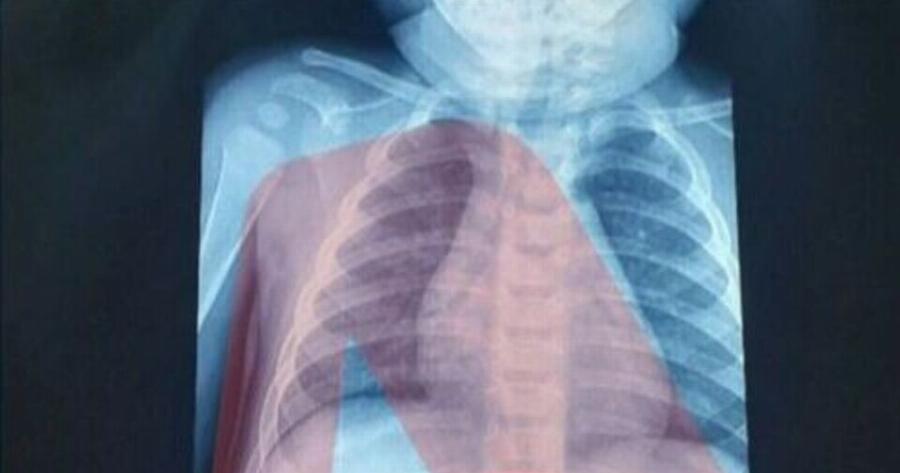

Με ένα απίστευτο περιστατικό ήρθαν αντιμέτωποι οι γιατροί σε νοσοκομείο Παίδων στην Αθήνα, όπου έφτασε 3χρονο αγοράκι που είχε καταπιεί ξυραφάκι.

Ένας 3χρονος μεταφέρθηκε εσπευσμένα στο νοσοκομείο, το οποίο κατάπιε ένα ξυραφάκι. Το παιδί αφού έφτασε σε Παίδων της Αθήνας, υποβλήθηκε άμεσα σε ακτινογραφία, η οποία έδειξε ότι όντως υπήρχε το αιχμηρό αντικείμενο στο στομάχι του

Όπως ενημέρωσαν οι γιατροί, τους γονείς του παιδιού, μετά την ακτινογραφία προσδιορίστηκε και το ακριβές σημείο όπου βρέθηκε το ξυραφάκι, ώστε οι χειρουργοί να προχωρήσουν σε επέμβαση αφαίρεσής του με ασφάλεια.